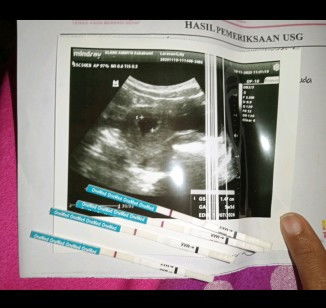

Udah nyobain ke RS sekalian kontrol soalnya sempet keluar darah kaya haid gitu di usia kehamilan 4 week sampe di rawat 4 hari tapi ps di USG katanya ngga hamil. Tapi skrng udah sebulan ngga ngalamin lagi keluar flek atau darah seperti haid tapi perut aga membesar klo Iyah hamil usia kandungan udah 9 minggu. kira² masih hamil ngga ya

Baca lagiaku jg gtu Bun tespek garis 1 tp USG udah 7 week udah ada CRL nya janinnya ukuran 1,22cm